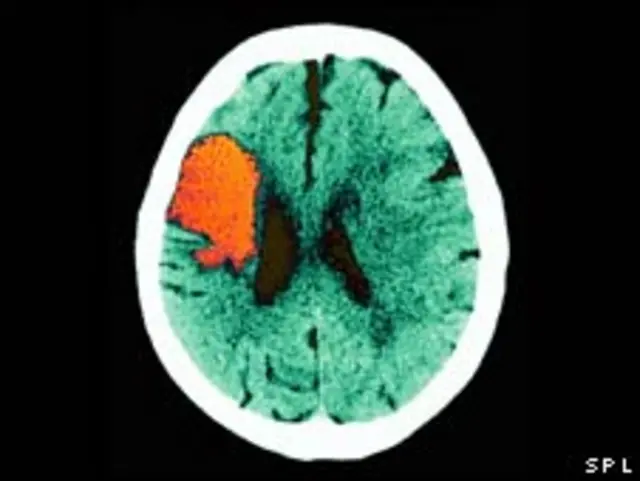

苏格兰研究人员称,降低体温可以帮助部分中风患者减少大脑损伤程度,增加生存几率。